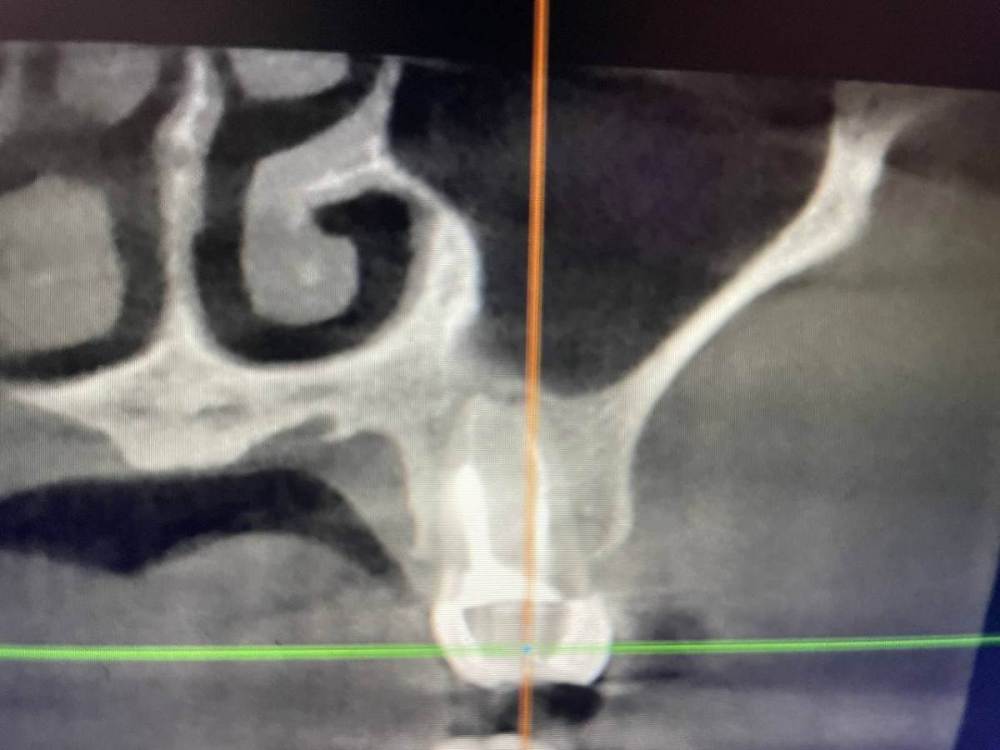

1586Doc Опубликовано 17 января, 2021 Автор Поделиться Опубликовано 17 января, 2021 еще один кейс.Утолщение слизистой гайморовой, хронический процесс на 25.26 зубахконтроль клкт через 8 месяцев Ссылка на комментарий

1586Doc Опубликовано 17 января, 2021 Автор Поделиться Опубликовано 17 января, 2021 первые 3 фото, ретрит 14 зуб4.5 фото 45 зуб. 4 Ссылка на комментарий